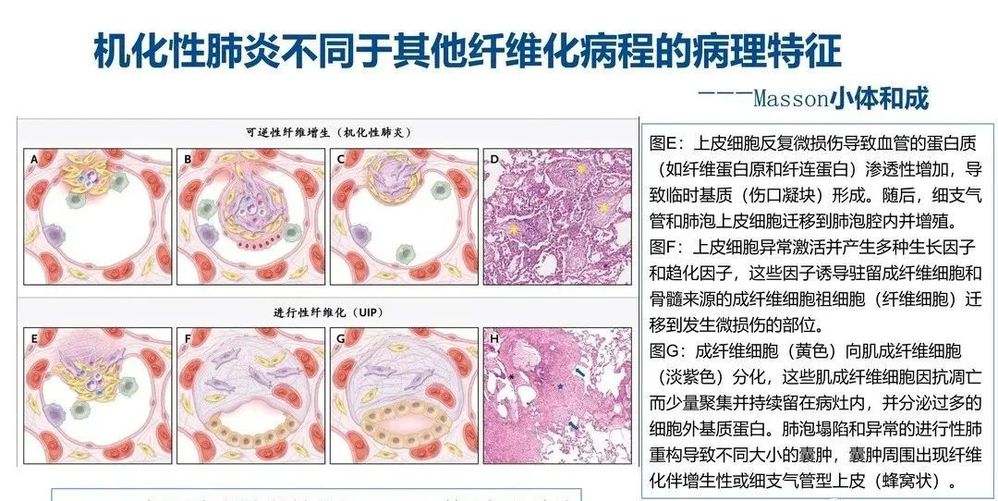

COP是炎性和纤维增生过程,以肺泡内纤维增生为特征,经过免疫抑制或抗炎治疗后可逆(有时不可逆)。

COP患者肺活检标本的组织病理学结果显示腔内有疏松结缔组织栓子,累及肺泡腔和肺泡管,也可累及细支气管,肺的基础结构保留。腔内疏松结缔组织栓子常以细柄连接到肺泡壁,并通过肺泡孔从一个肺泡延伸到相邻的肺泡,形成特征性的蝴蝶状结构。肺泡壁可出现轻度慢性炎症(如涉及淋巴细胞和浆细胞)。

观察到以下情况时,提示有其他诊断:显著的间质慢性炎症(涉及中性粒细胞或嗜酸性粒细胞)、形态不良的肉芽肿、细支气管周围化生、淋巴样聚集、血管炎、间质纤维化或镜下蜂窝状改变。

COP的主要病理变化是肺泡内、肺泡管、呼吸性细支气管及终末细支气管内有息肉状肉芽组织增生,形成Masson小体,其病变表现单一,时相一致,呈斑片状和支气管周围分布,位于气腔内,含极少炎性细胞,肺结构往往正常。肺泡腔内肉芽组织呈芽生状,由疏松的结缔组织将成纤维细胞包埋而构成,可通过肺泡孔从一个肺泡扩展到邻近的肺泡,形成典型的“蝴蝶影”。肉芽组织中可存在炎性细胞,尤其在疾病早期,可见单核细胞、巨噬细胞及少量的肥大细胞、嗜酸粒细胞、中性粒细胞。在空的肺泡腔内可见肺泡巨噬细胞,部分肺泡巨噬细胞呈泡沫状,伴有Ⅱ型肺泡上皮细胞增生。受累的肺泡间隔有少量淋巴细胞和浆细胞浸润为主的轻度炎性渗出,肺泡间隔稍增厚。